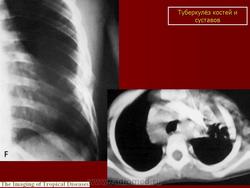

Туберкулез костей и суставов.

Костно-суставной туберкулез должен рассматриваться как одно из местных проявлений общего туберкулезного процесса, развивающегося в целостном организме.

Распространение туберкулезного процесса происходит гематогенным путем. Согласно современным представлениям, наиболее чувствительной к первичному заражению является костная ткань, богатая костным мозгом. Синовиальная оболочка невосприимчива к гематогенному заражению, однако поражается вторично при разрастании гранулемы из сформированного уже очага. Хрящевая ткань также не восприимчива к первичному заражению, наиболее устойчива, и в определенной степени, выполняет буферную роль, предупреждая переход процесса с кости на сустав. Следовательно, туберкулезный процесс в костной ткани наиболее часто локализуется в отделах, богатых костным мозгом - в телах позвонков, эпифизарных отделах длинных трубчатых костей, в губчатых костях, и реже в диафизарных отделах коротких и длинных трубчатых костей. Почти каждый туберкулезный артрит следует рассматривать как последующую фазу первично возникающего в околосуставных отделах костного фокуса.